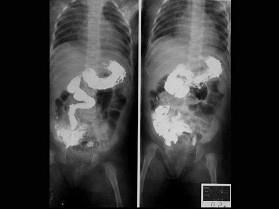

问题 女婴,出现持续性呕吐,腹胀,如图所示,最可能的诊断为?(?)

选项 A.肠梗阻 B.肠扭转 C.肠闭锁 D.肠旋转不良 E.肠穿孔

答案 D